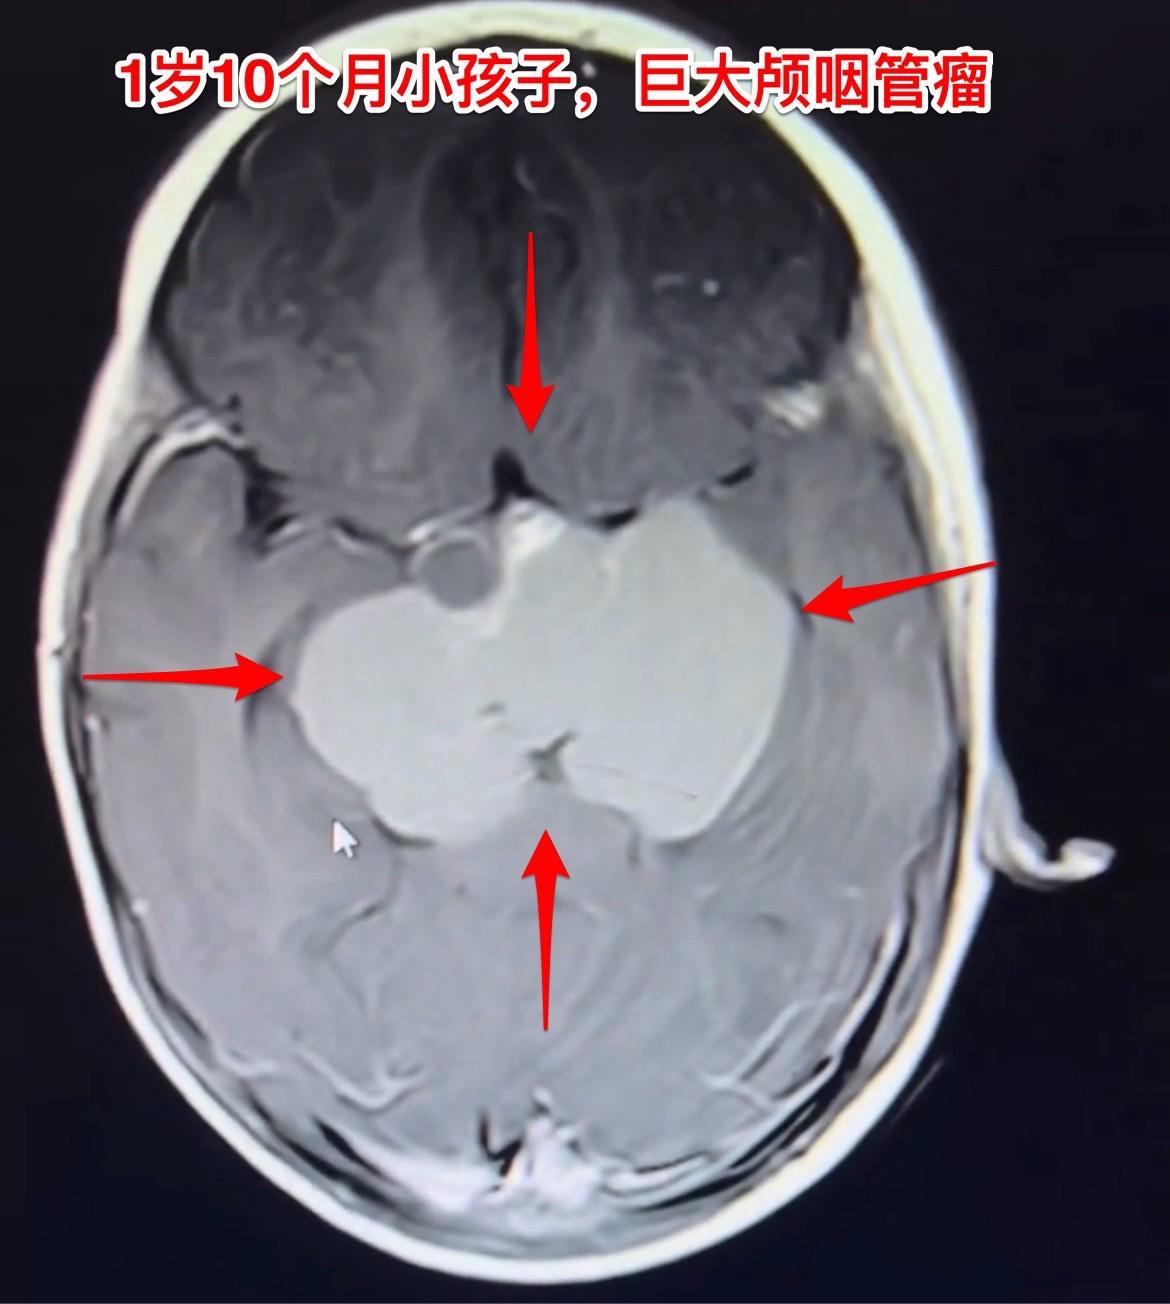

一岁十个月小孩子颅咽管瘤手术后11天。身体终于缓过来了! 现在她的精神状态好,能吃能喝,和家长交流也没有障碍,能看见手机视频。左侧眼睑下垂症状改善了,两个眼睛看起来是对称的。 由于颅咽管瘤体积大,刚刚做完手术时,小朋友身体很弱,出现贫血、低蛋白血症、电解质紊乱。有一次低钠血症还造成癫痫发作。 好事多磨!经过精心治疗和护理,小朋友熬过了一关又一关!近期有望出院了。颅咽管瘤眼睑下垂